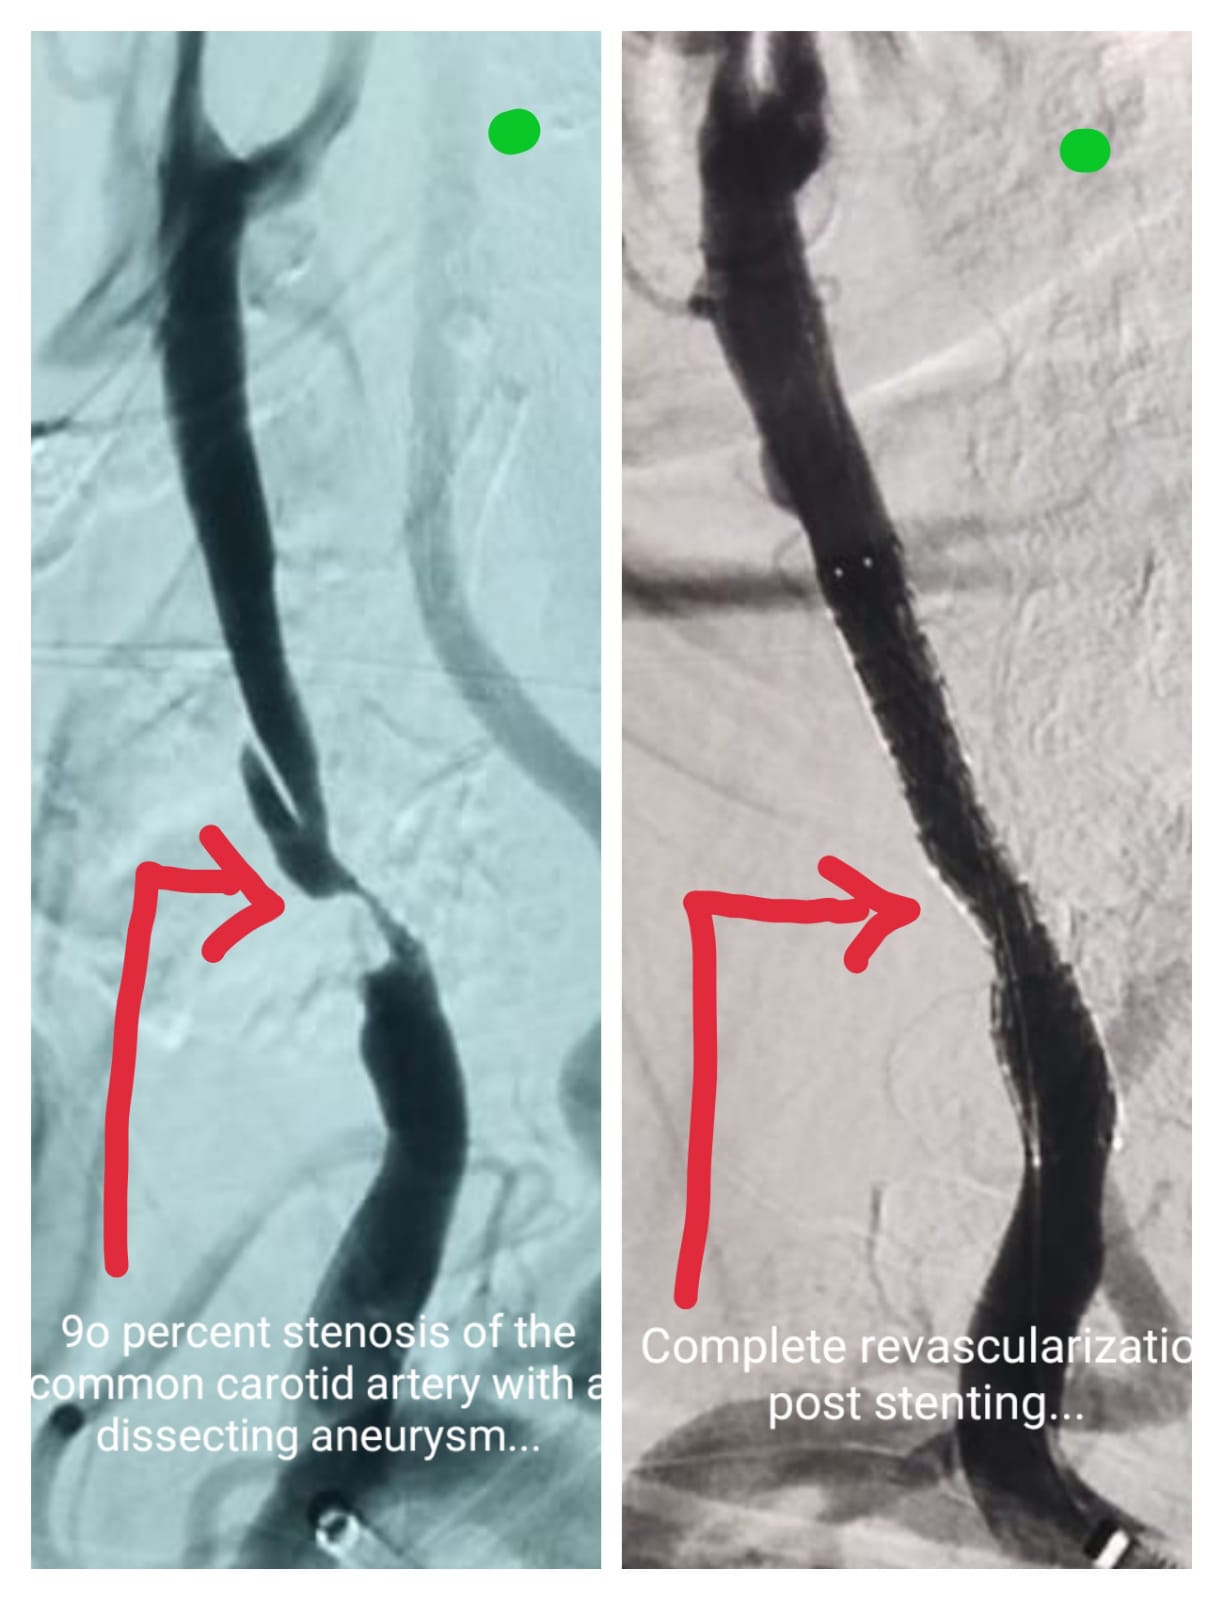

Carotid Artery Stenting Procedure Pre procedure - 95% stenosis in Internal Carotid Artery Post Procedure- Deploy Stent & restore complete blood flow